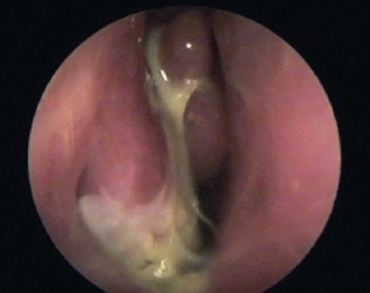

Eine kugelige homogene Verschattung in der Höhle wird im Rahmen der zahnmedizinischen und HNO-Behandlung häufig beobachtet (Abb. 5). Schmerz oder Druckgefühl werden in der Regel nicht angegeben. Bei diesen Retentionszysten handelt es sich oft um Zufallsbefunde, die bei bis zu 14% der Bevölkerung industrialisierter Länder gesehen wurden. Sie sind die Folge umschriebener intraepithelialer Sekretstörungen der Sinusschleimhaut und bedürfen im Falle klinischer Beschwerdefreiheit keiner Behandlung. Nur sehr große Zysten oder homogene Totalverschattungen sollten therapiert werden (Abb. 6). Häufig beklagen die Betroffenen ablaufende Nasensekrete mit unangenehmem Geruch und Geschmack. Im mittleren Nasengang sind endoskopisch eingedickte Sekretbefunde sichtbar (Abb. 7). Besondere Beachtung benötigen inhomogene Verschattungen mit gegebenenfalls sehr dichten Einschlüssen. Hier sind spezifische Infektionen (Pilzball), Tumoren oder Fremdkörper suspekt. Auch im Falle einer deutlichen Restbelüftung muss die Kieferhöhle exploriert und der Befund histologisch geklärt werden (Abb. 8a bis d).